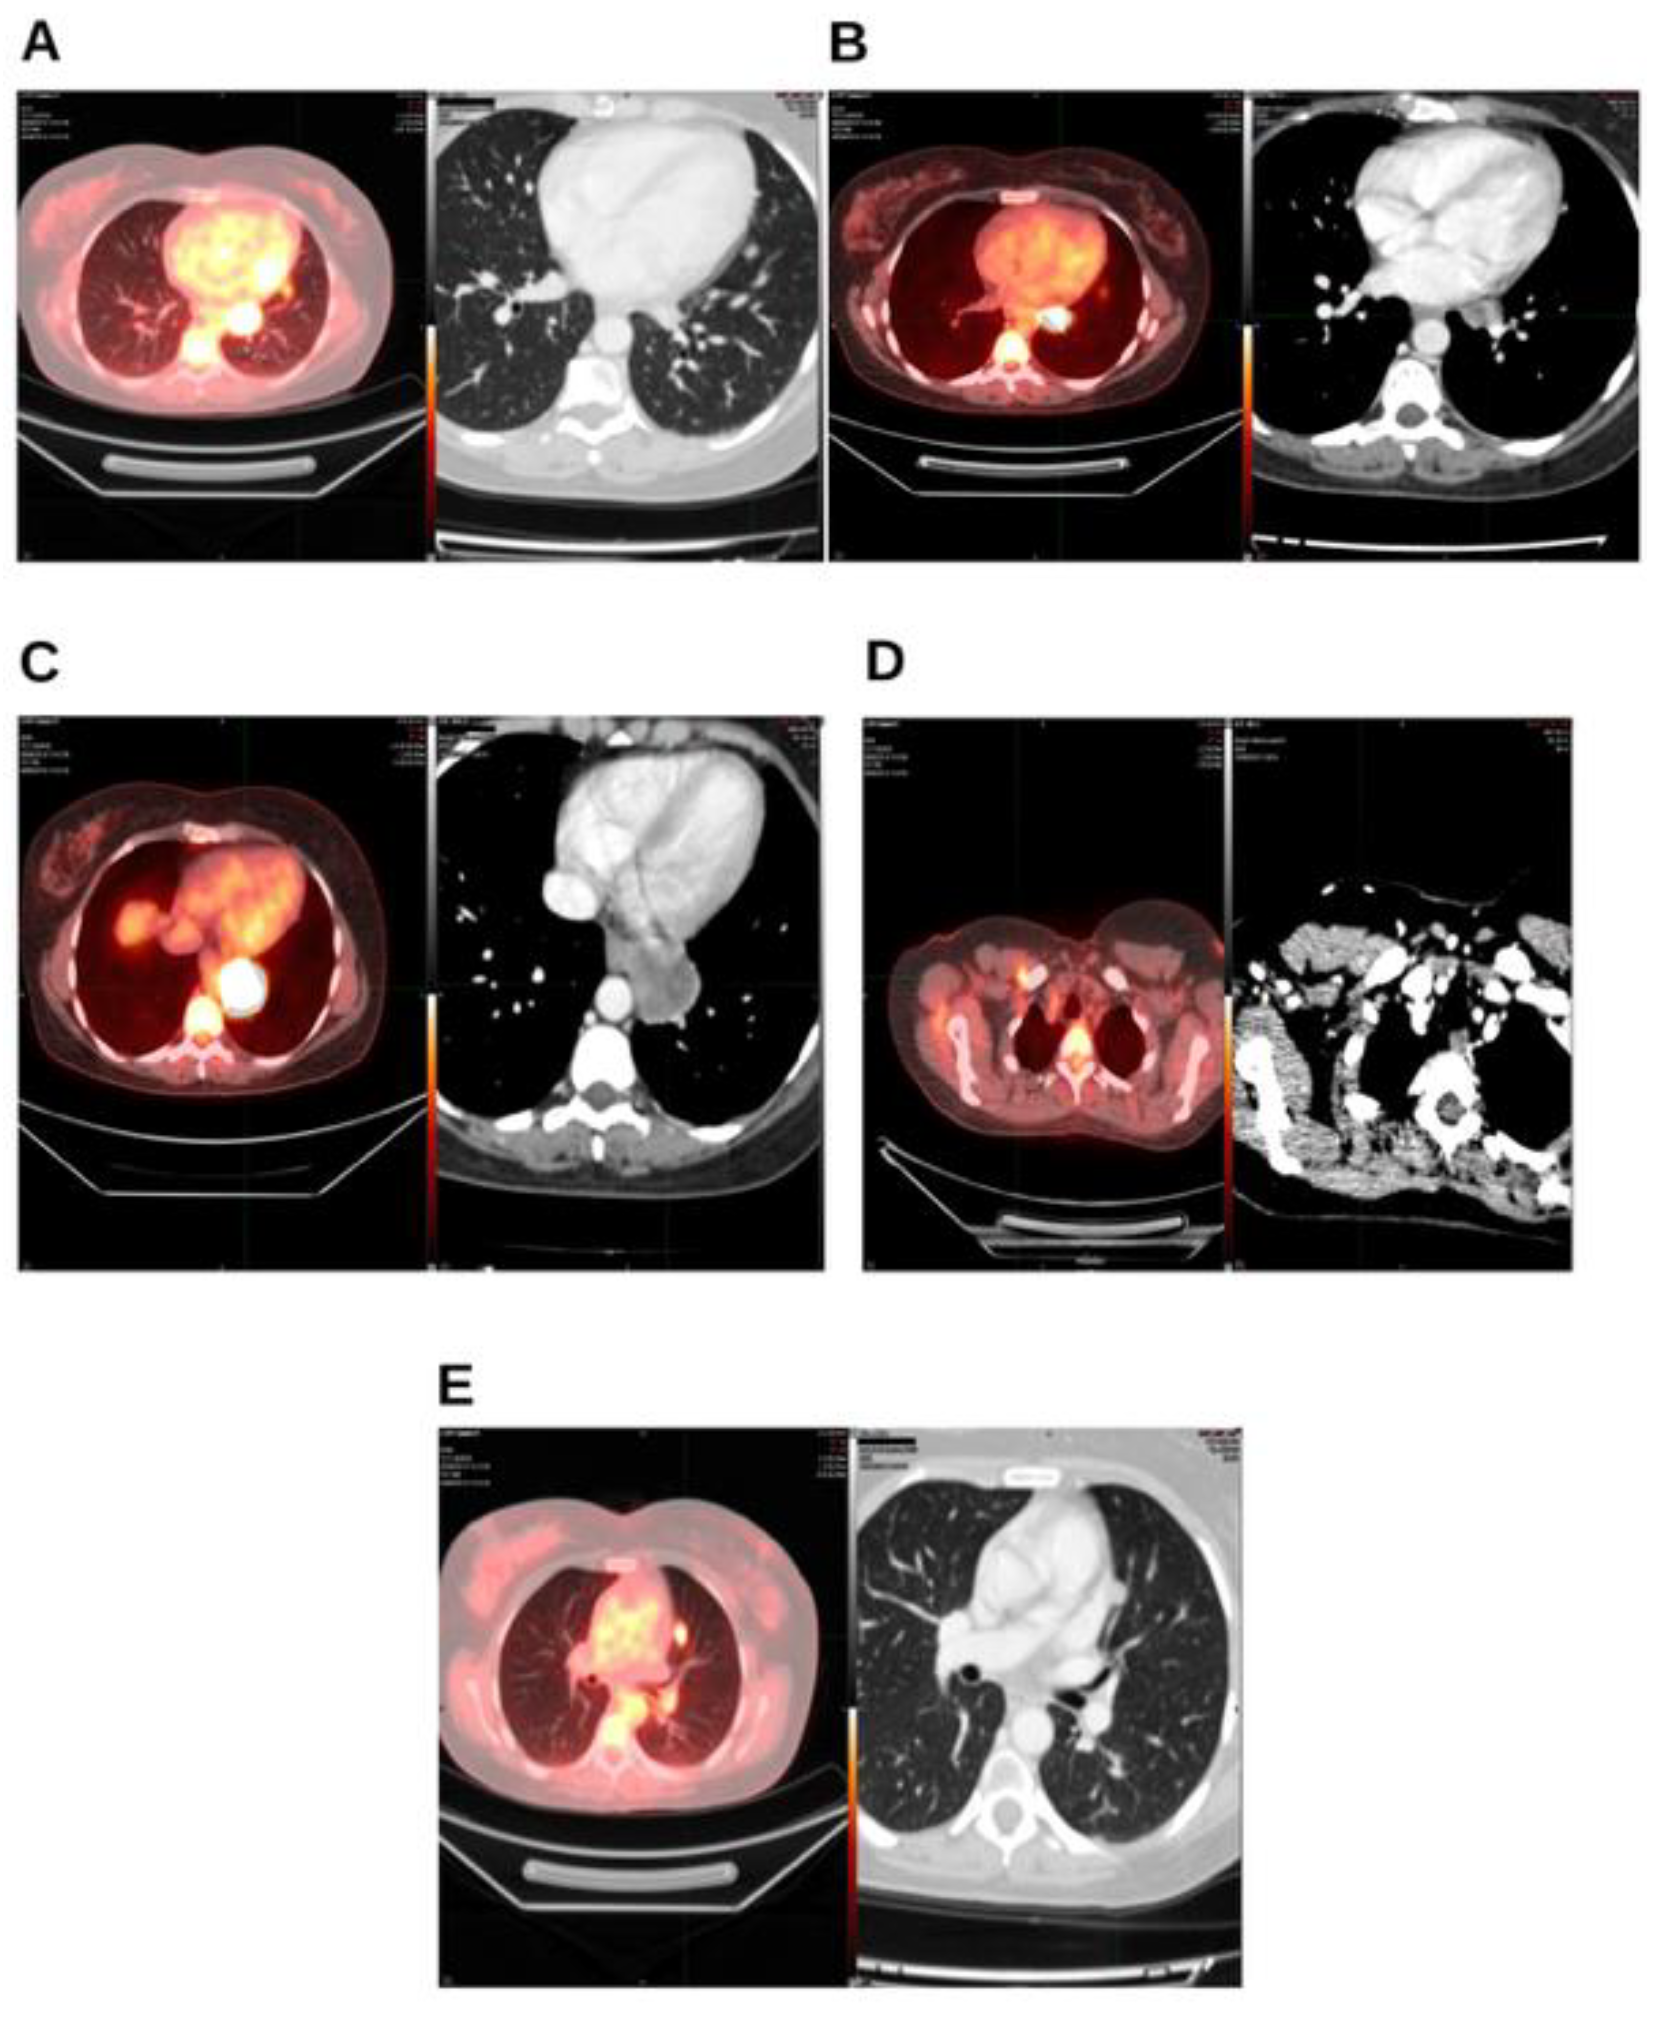

Background and Clinical Significance: Breast cancer is the most frequent malignancy in women. Advanced metastatic breast cancer is considered a treatable but incurable condition, with a median overall survival of only 2-3 years. Among its subtypes, triple-negative breast cancer (TNBC) accounts for a high proportion of breast cancer–related deaths. It is characterized by an aggressive clinical course, early recurrence, and a strong propensity for visceral and brain metastases. Case Presentation :We report the case of a Caucasian woman who, two years after being initially diagnosed and treated for TNBC, developed disease relapse with lung and mediastinal lymph node metastases. The patient received three months of chemotherapy combined with an adjuvant integrative protocol consisting of melatonin, cannabidiol, and oxygen–ozone therapy. This combined approach led to the complete disappearance of the lung nodules. Subsequently, stereotactic radiotherapy was performed and, in association with the ongoing integrative treatment, resulted in a significant reduction of mediastinal adenopathy. Introduction of immunotherapy, supported continuously by the same adjuvant strategy, achieved a complete and durable remission. Strikingly, the patient remained disease-free five years after the diagnosis of lung and mediastinal metastases. Conclusions: This clinical case highlights the potential benefit of using melatonin, cannabidiol, and oxygen–ozone therapy as part of an integrative approach in patients with aggressive metastatic TNBC. While it is not possible to establish causality from a single case, the sustained remission observed suggests that such unconventional adjuvant strategies could play a supportive role in enhancing the efficacy of standard oncologic therapies.